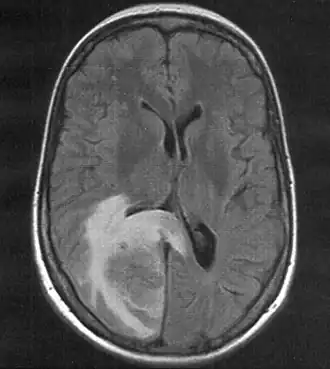

Skull MRI (T2 flair) of a brain metastasis with accompanying edema

Serial neuroimaging (CT scans and magnetic resonance imaging) can be useful in diagnosing or excluding intracranial hemorrhage, large masses, acute hydrocephalus, or brain herniation as well as providing information on the type of edema present and the extent of affected area.[1][3] CT scan is the imaging modality of choice as it is widely available, quick, and with minimal risks.[1] However, CT scan can be limited in determining the exact cause of cerebral edema in which cases, CT angiography (CTA), MRI, or digital subtraction angiography (DSA) may be necessary. MRI is particularly useful as it can differentiate between cytotoxic and vasogenic edema, guiding future treatment decisions.[1]